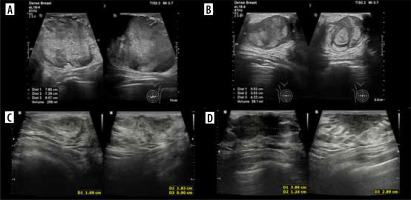

The patient was admitted to our centre for further diagnosis and treatment. On US almost complete involvement of both breasts by heterogeneous, irregularly vascularised nodules was described; in the left breast, the largest ones were located centrally, and had approximately 78 × 73 × 86 mm on the left and 50 × 35 × 42 mm on the right (Figures 9A and B). Additionally, numerous enlarged lymph nodes and a metastasis in the mastoid attachment of the right sternocleidomastoid muscle were found. WB-MRI revealed multiple lesions consistent with metastases throughout the body. On PET-CT, all of them showed increased metabolism of 18F-FDG.

Figure 9

Two ultrasound (US) examinations of breast metastases in Patient no. 4. A, B) Initial examination in our centre. A) The largest nodule in the left breast. B) The largest nodule in the right breast. C, D) The second US after the 4th cycle of chemotherapy. Partial regression of the lesions. C) Nodule in the left breast. D) Nodule in the right breast

The patient was qualified for chemotherapy (VAC), and partial regression of the metastatic and primary lesions was initially achieved (Figures 9C and D).

Subsequently, the decision was made to excise metastases from the breasts and administer radiotherapy to the primary tumour. Despite treatment, progression occurred, with new lesions in the breasts and numerous metastases in bones, lymph nodes, lungs, pleura, and soft tissues of the head, chest, right thigh, and left shin (Figure 10).

Figure 10

Magnetic resonance imaging study shows the progression of the disease in Patient no. 4 with new lesions in both breasts and nodules in the pleura. A-D) WATER/T1 post-Gd, axial plane